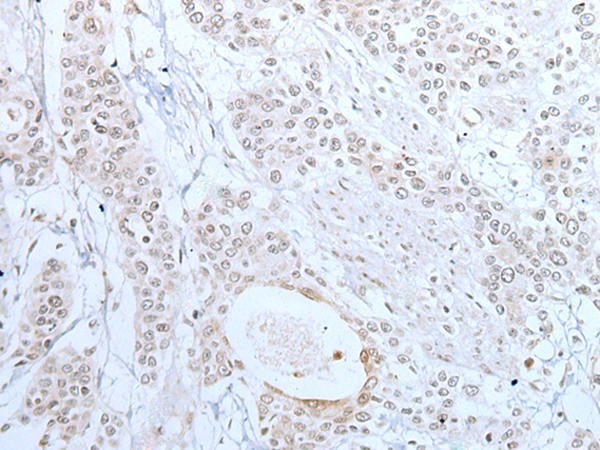

IHC positive control: |

Human prostate cancer and human tonsil |